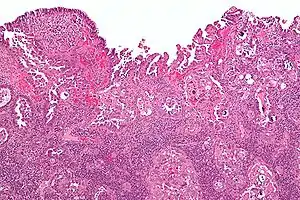

| Histology H&E of uterine serous papillary carcinoma. H&E stain. | |

Histopathologically, uterine serous carcinomas is typically characterized by (1) nipple-shaped structures (papillae) with fibrovascular cores (2) marked nuclear atypia (irregularities in the nuclear membrane, enlarged nuclear size), (3) psammoma bodies and (4) cilia.